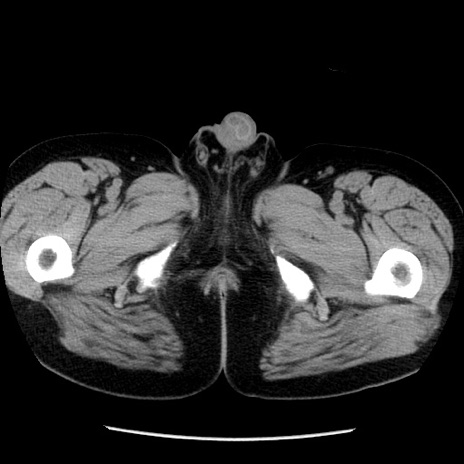

症例29(横断像)

【症例】40歳代男性

【現病歴】2日前から胃痛あり。徐々に周期的な激痛に変化した。本日になっても激痛があるため受診。

【身体所見】意識清明、BT 38-39℃台あり、腹部:膨満、やや硬、右下腹部に圧痛あり。

【データ】WBC 8500、CRP 23.26